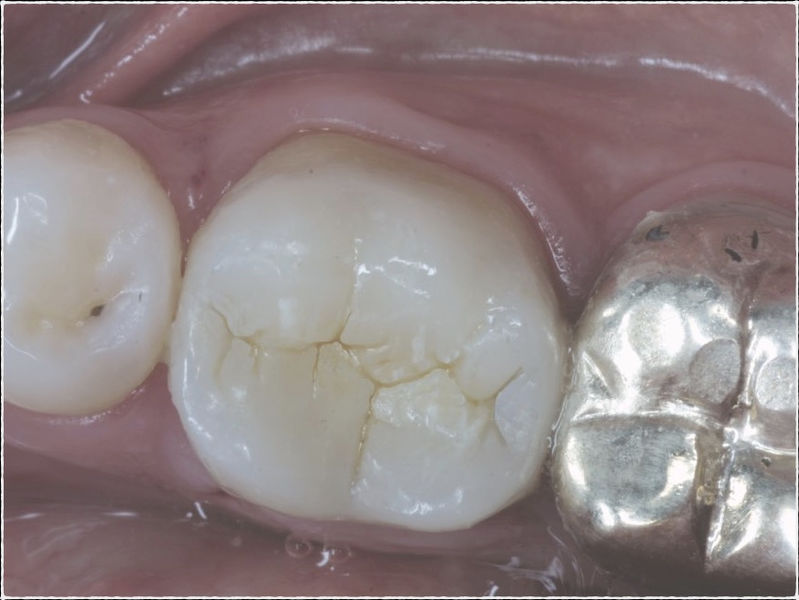

Disciplina fundamental de la Odontología enfocada en el diagnóstico, prevención y tratamiento restaurador de las piezas dentales que han sufrido daños. Su objetivo principal es devolver al diente su equilibrio biológico, funcional y estético cuando su integridad ha sido alterada. Resinas directas, incrustaciones, coronas.

La restauración de un diente tras una endodoncia, es crucial para su supervivencia a largo plazo, ya que el procedimiento puede debilitar la estructura dental. El tipo de restauración elegido depende principalmente de la cantidad de estructura dental remanente después de la endodoncia. Principalmente se usan incrustaciones, coronas y/o postes.

Restauraciones fabricadas en el laboratorio con materiales estéticos, los cuales cubren de manera parcial dientes posteriores. Se utilizan primariamente para restaurar dientes con caries, fracturas y/o defectos amplios. Para poder enviar el caso al laboratorio se toman impresiones utilizando materiales de impresión o técnicas modernas digitales.

Restauraciones fabricadas en el laboratorio con materiales estéticos, los cuales cubren de manera total dientes anteriores y posteriores. Se utilizan primariamente para restaurar dientes con caries, fracturas y/o defectos amplios, así como soportes de puentes. Para poder enviar el caso al laboratorio se toman impresiones utilizando materiales de impresión o técnicas modernas digitales.